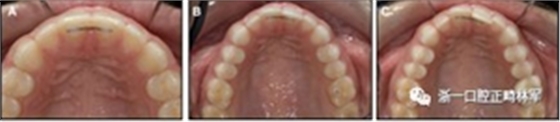

圖10.柔性螺旋弓絲通過(guò)中切牙的緩慢移位和旋轉(zhuǎn)移位保持上頜中央間隙:A,放置后即刻; B,4年后; C,8年后。